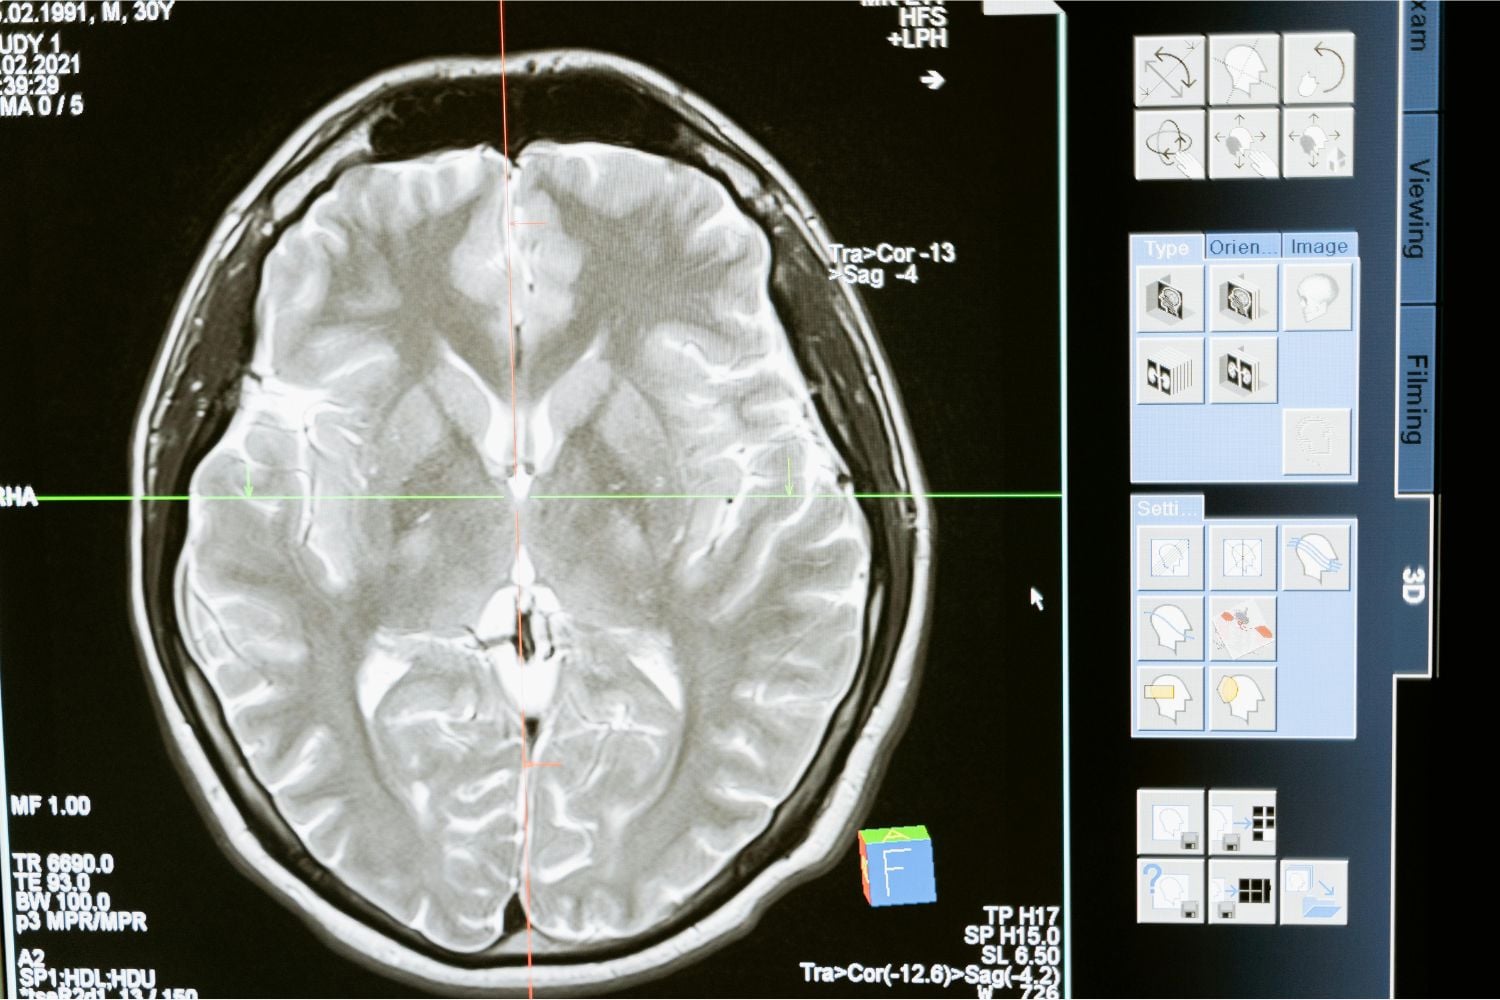

Los neurólogos advierten que durante un accidente cerebrovascular isquémico (provocado por la obstrucción de una arteria) mueren alrededor de dos millones de neuronas por minuto. En apenas una hora, el cerebro puede envejecer el equivalente a más de tres años. En ese contexto, el tiempo no es solo un factor clínico: es un determinante de vida o muerte.

La trombectomía endovascular es actualmente el tratamiento de referencia para los ACV causados por coágulos que bloquean el flujo sanguíneo al cerebro. Se trata de una intervención altamente especializada: un cirujano introduce catéteres a través de los vasos sanguíneos, normalmente desde la ingle, y los guía hasta el punto exacto de la obstrucción para retirar el coágulo.

Este procedimiento requiere equipos sofisticados, imágenes por rayos X en tiempo real y la experiencia de neurocirujanos o radiólogos intervencionistas altamente entrenados. Por esa razón, su disponibilidad suele concentrarse en grandes hospitales urbanos.